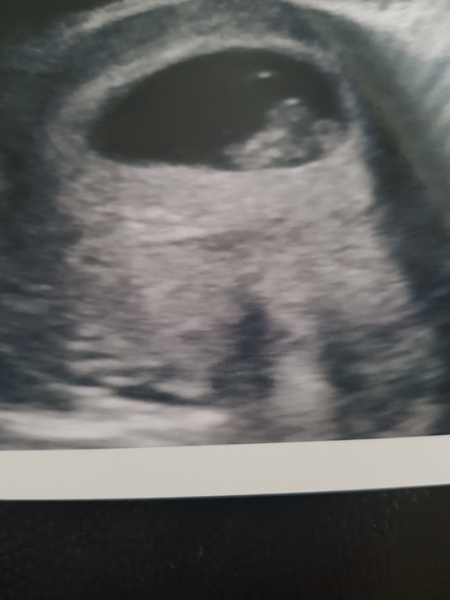

Heres my little bean.

Apparently I have a backwards tilted uterus, she said its nothing to worry about. I don't really know much about that so going to do some googling!

CuppaSarah I know, its surreal. I keep looking at the photo amazed that its growing inside of me. It looks like it has two heads in the photo but I was assured its one head and a yolk sac 😂

Love that scan Sals. I have s tilted uterus too and apparently according to the doctor the only difference is blurrier scans this early as it's harder to see and more back pain.